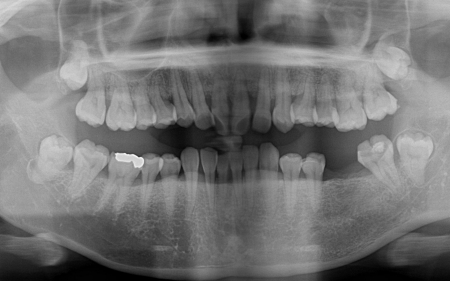

加えてレントゲン検査では、上前歯を中心に歯を支える骨が減少していることも確認できました。

しかし今回は、歯周内科治療によって十分な改善が確認できたため、外科処置は行わず左下のブリッジ治療へと進むことができました。

歯周内科治療から左下ブリッジの治療まで、全体の治療期間は約6ヶ月で終了しています。

画像をクリックすると拡大・詳細コメントを確認いただけます